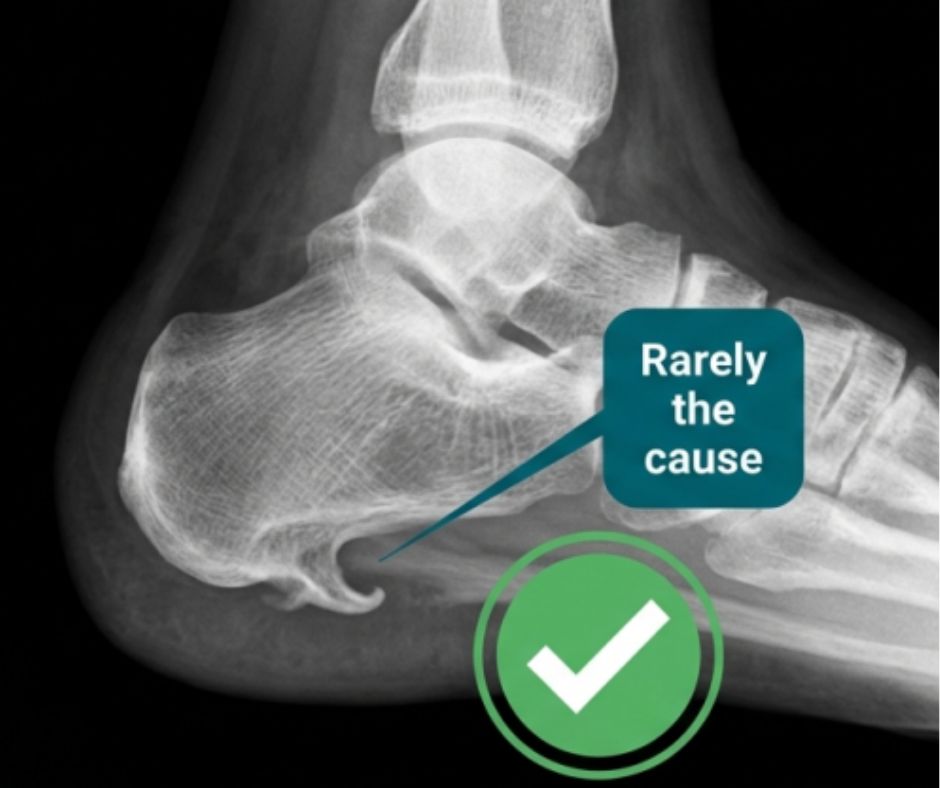

Many patients worry after seeing a heel spur on an X ray. The spur is often a sign of long term traction, but it is rarely the main source of pain.

Clinical reality: We treat fascia tightness and irritation. We do not chase the spur.

Heel spur seen on X ray, often not the cause of first step morning heel pain in plantar fasciitis

A heel spur on X ray is often a result of long term traction. In many patients, the main pain source is plantar fascia soft tissue irritation, not the spur itself.